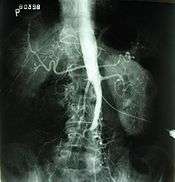

Plate from Gray's Anatomy showing the abdominal aorta and the common iliac arteries. | |

In medicine, aortoiliac occlusive disease, also known as Leriche's syndrome and Leriche syndrome, is a form of peripheral artery disease involving the blockage of the abdominal aorta as it transitions into the common iliac arteries.